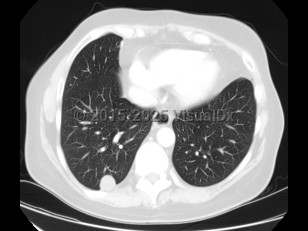

The second most common presentation is pulmonary nodules. Patients are usually asymptomatic but may present with cough, hemoptysis, fever, and chest pain. Most frequently, however, infection in these patients presents as a solitary nodule on chest radiographs, and the diagnosis is usually made on pathology (done to rule out other serious conditions; see Differential Diagnosis & Pitfalls). Dirofilaria immitis is the most common cause of pulmonary lesions, although D. repens has also been reported.